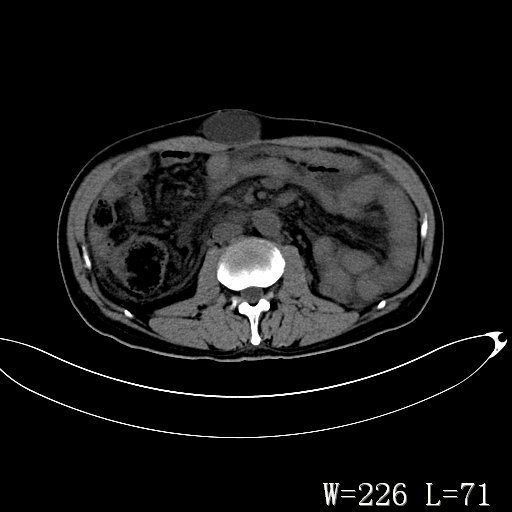

标题: CT27080:腹壁肿物?

男,52岁,门脉高压断流术后1年,发现腹部肿物2月。

1)前腹壁中线区(脐上方)囊性占位性病变,考虑淋巴囊肿。2)腹水。